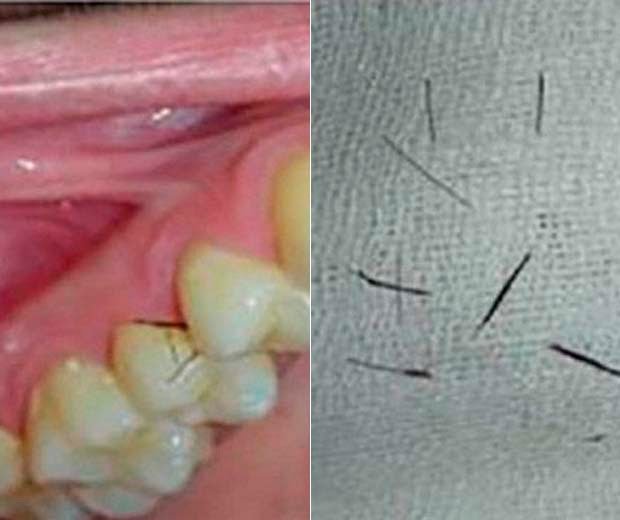

Itália -| Uma mulher notou o surgimento de pêlos parecidos com cílios nas gengivas em 2009, quando ela tinha 19 anos. Inicialmente, a italiana foi diagnosticada com síndrome do ovário policístico. A paciente foi submetida a cirurgia na boca e a tratamento com anticoncepcionais. Porém, seis anos depois, os “cílios” voltaram a crescer nas gengivas da mulher, após ela interromper a medicação.

Uma condição rara faz com que uma paciente na Itália desenvolva o crescimento de pelos parecidos com cílios nas gengivas, de acordo com relato publicado na revista médica “Oral Surgery, Oral Medicine, Oral Pathology and Oral Radiology”.

O crescimento exagerado de pelos especialmente no rosto, no peito, nas costas e nas nádegas, é comum em quadros de síndrome do ovário policístico. Porém a ocorrência em gengivas é raramente vista.

“A ocorrência de pelos na cavidade oral é extremamente rara. A literatura médica registra apenas cinco casos. Na maior parte, de apenas um pelo em vários locais da cavidade oral”, disse Felice Femiano, autor do relato.